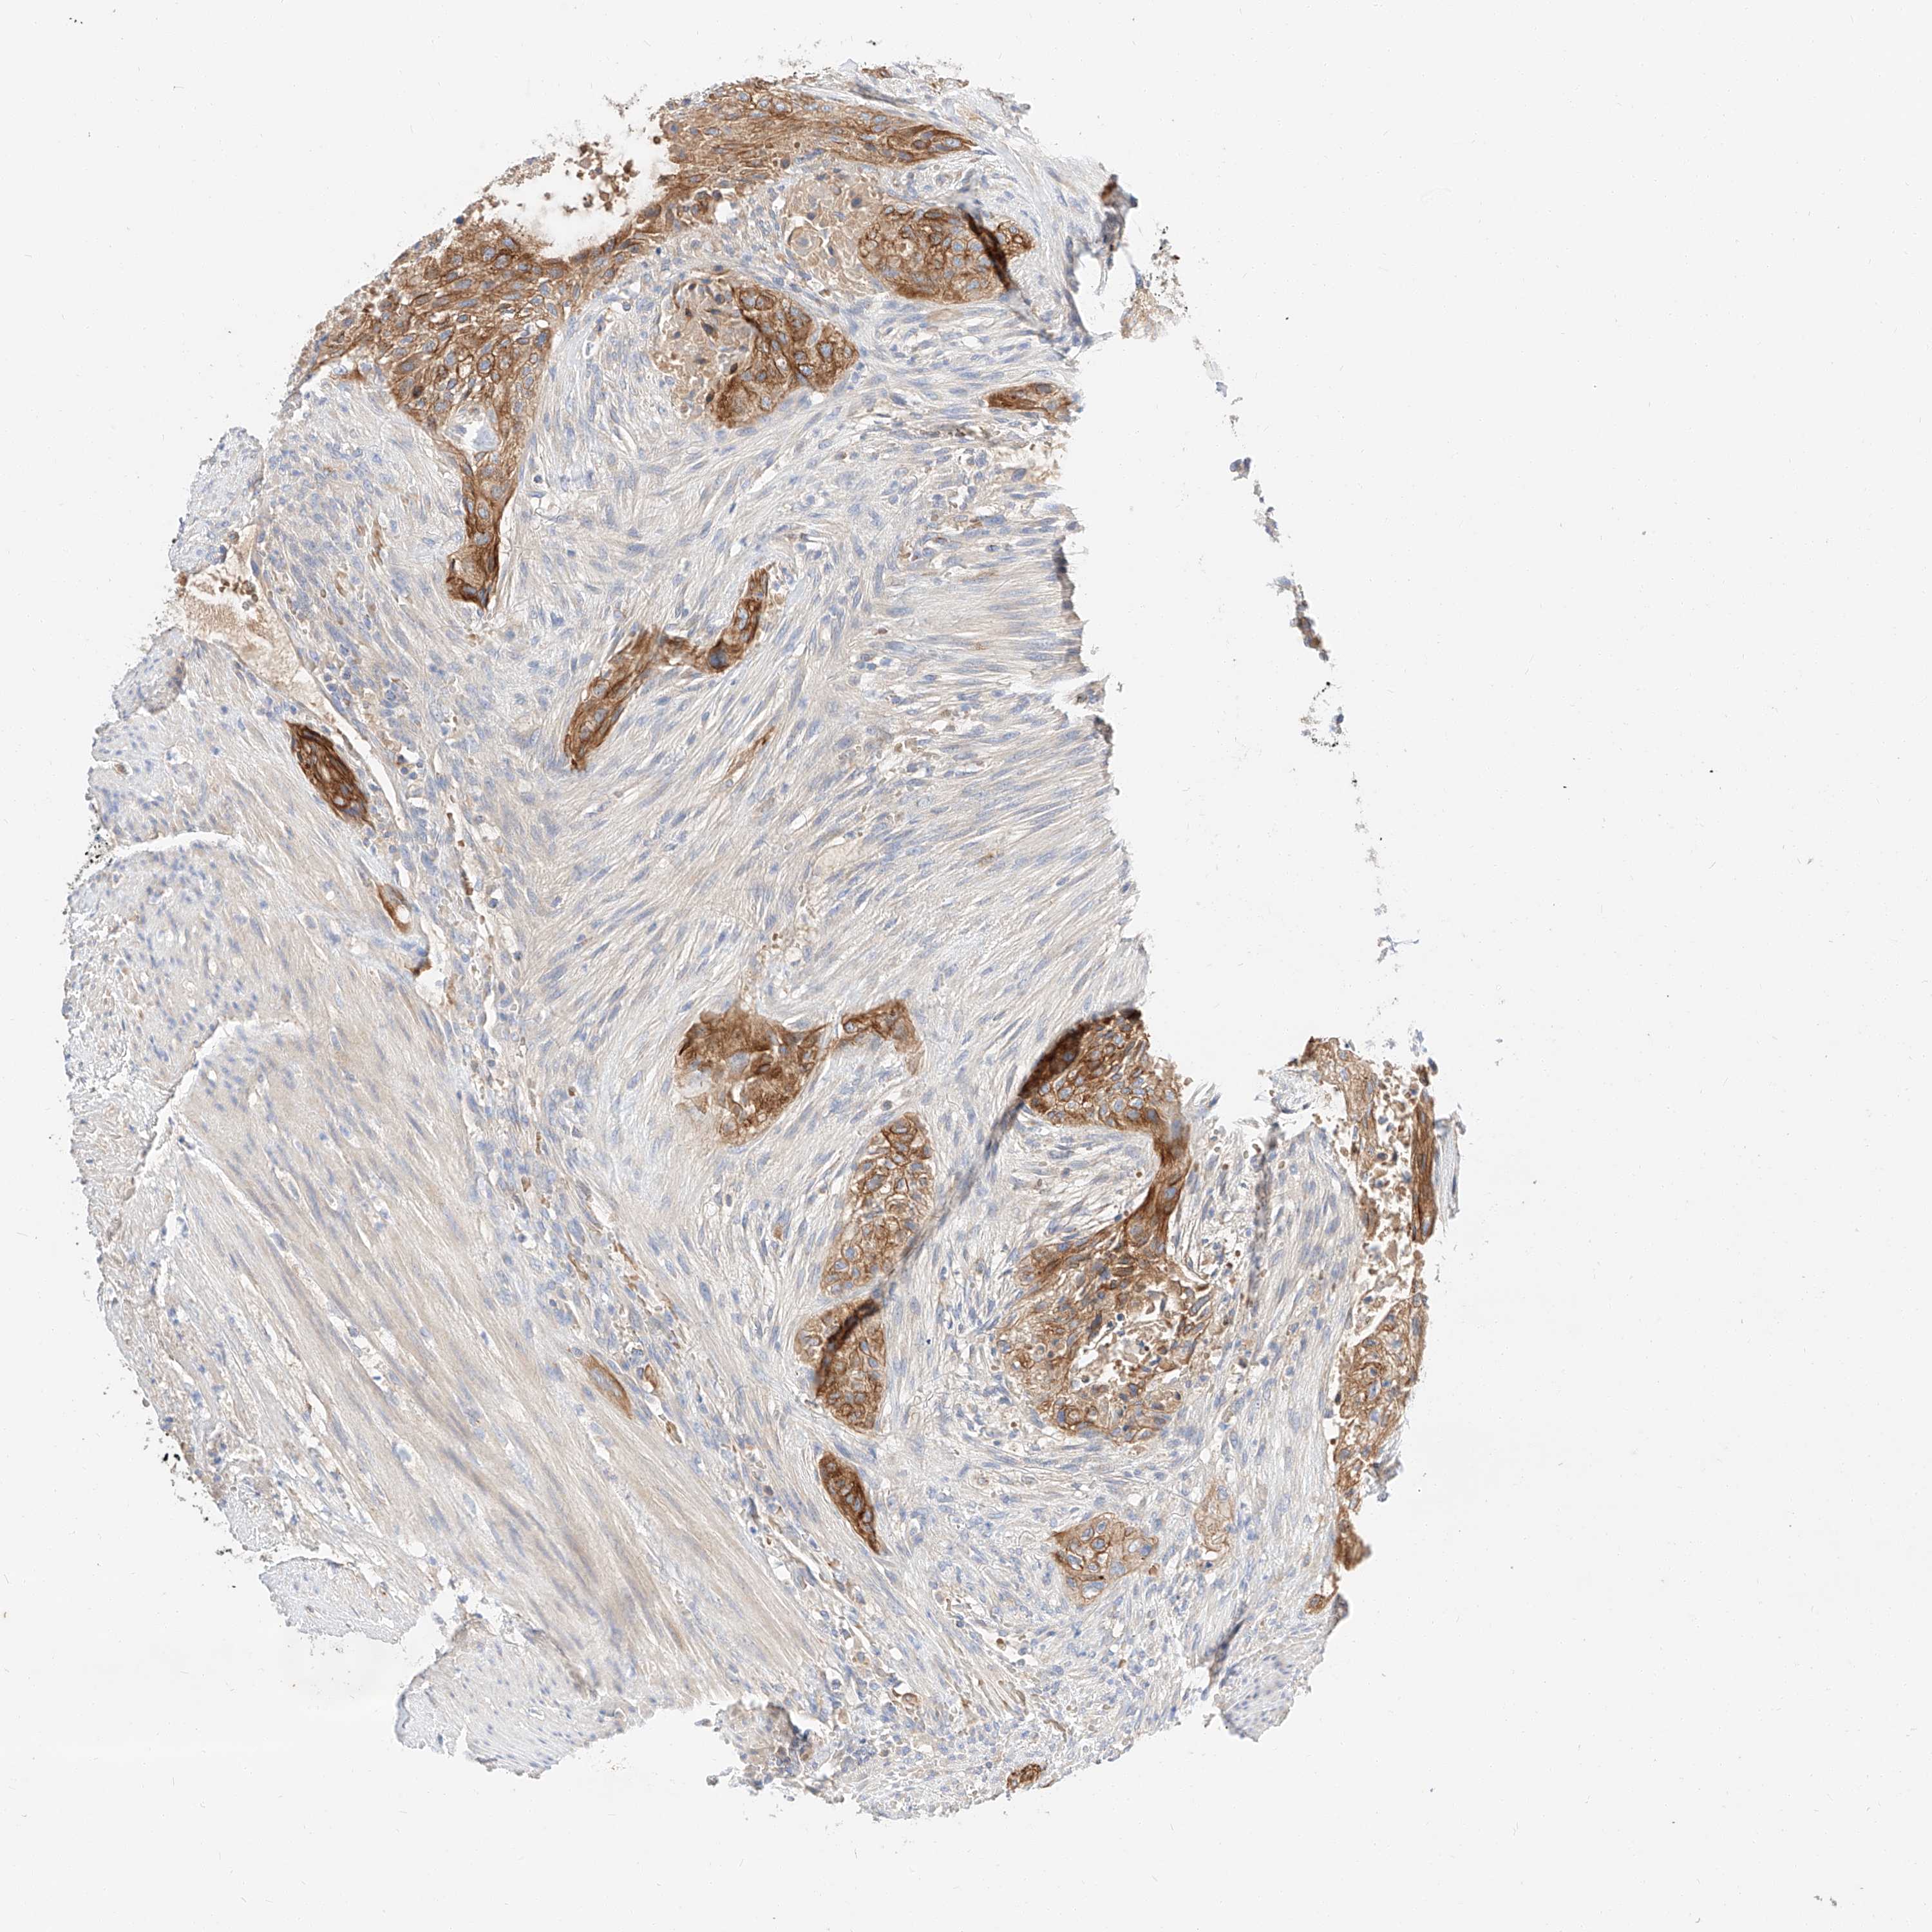

UROTHELIAL CANCER - Protein expressioni

A mouse-over function shows sample information and annotation data. Click on an image to view it in a full screen mode. Samples can be filtered based on level of antibody staining by selecting one or several of the following categories: high, medium, low and not detected. The assay and annotation is described here.

Note that samples used for immunohistochemistry by the Human Protein Atlas do not correspond to samples in the TCGA dataset.

Antibody stainingi

Antibody staining in the annotated cell types in the current human tissue is reported as not detected, low, medium, or high, based on conventional immunohistochemistry profiling in selected tissues. This score is based on the combination of the staining intensity and fraction of stained cells.

Each image is clickable and will lead to virtual microscopy that enables deeper exploration of all samples and also displays staining intensity scores, fraction scores and subcellular localization as well as patient and tissue information for each sample.

Antibody HPA029712

Antibody HPA029713

Staining

High

Medium

Low

Not detected

Intensity

Strong

Moderate

Weak

Negative

Quantity

>75%

75%-25%

<25%

None

Location

Nuclear

Cytoplasmic/membranous

Cytoplasmic/membranous,nuclear

Urothelial carcinoma, Low grade

Urothelial carcinoma, High grade